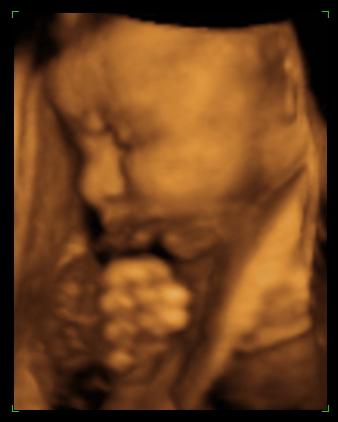

oldalnézet

egy bukfenc

és ismét hason 2008.02.08 10:09